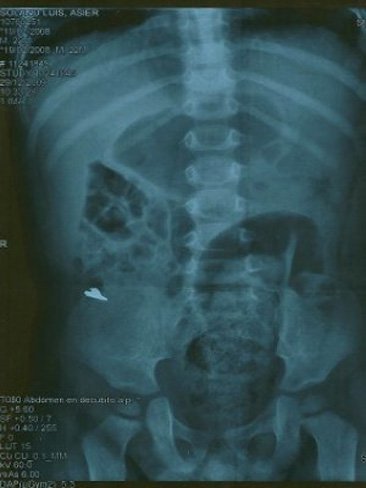

Ante la incredulidad del padre y la insistencia de la madre, el niño fue llevado a urgencias donde lo examinaron primero con un detector de metales para evitar una radiación innecesaria. Se llevaron una gran sorpresa cuando el aparato empezó a pitar y luego se confirmó con una radiografía que la cuchilla había pasado por el esófago hasta el estómago del bebé sin causar, afortundamente ningún daño. Le pusieron una dieta rica en fibra y a los pocos días expulsó la cuchilla en una deposición.